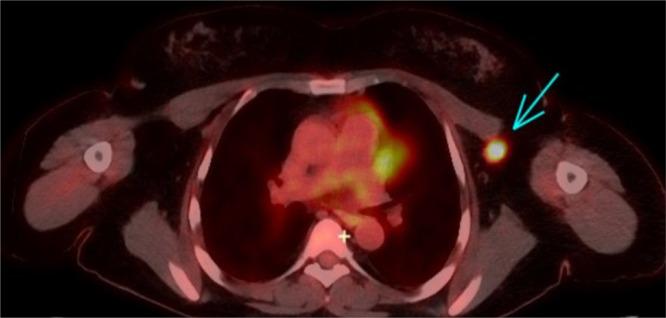

Basal cell carcinoma (BCC) is the most common nonmelanoma skin cancer but rarely metastasizes, with an estimated metastatic rate of 0.1%. Metastatic spread to axillary lymph nodes is extremely uncommon, and to our knowledge, no prior cases have reported incidental detection on screening mammography. We report the case of a 48-year-old Caucasian female with a history of renal transplants, chronic immunosuppression, and multiple biopsy-confirmed BCCs and cutaneous squamous cell carcinomas who presented with a new axillary mass incidentally found on screening mammography. Final pathology following axillary lymph node dissection revealed metastatic BCC. This case illustrates the diagnostic complexity of axillary masses found on screening mammography and underscores the need for vigilant evaluation of BCC metastases in immunosuppressed patients. It highlights the diagnostic limitations of imaging and core biopsy in distinguishing BCC from cutaneous squamous cell carcinomas or metastatic breast carcinoma. Given the poor prognosis of metastatic BCC, this report supports more proactive imaging strategies in high-risk individuals and emphasizes the need for further research into optimal management.

基底细胞癌(BCC)是最常见的非黑色素瘤皮肤癌,但很少发生转移,估计转移率为0.1%。转移至腋窝淋巴结极为罕见,据我们所知,此前尚无在乳腺钼靶筛查时偶然发现转移的病例报道。我们报告一例48岁的白种女性,有肾移植、慢性免疫抑制病史,且经多次活检确诊患有基底细胞癌和皮肤鳞状细胞癌,其在乳腺钼靶筛查时偶然发现腋窝有一新肿块。腋窝淋巴结清扫术后的最终病理显示为转移性基底细胞癌。该病例说明了乳腺钼靶筛查时发现腋窝肿块的诊断复杂性,并强调了对免疫抑制患者基底细胞癌转移进行警惕性评估的必要性。它突出了影像学检查和粗针活检在区分基底细胞癌与皮肤鳞状细胞癌或转移性乳腺癌方面的诊断局限性。鉴于转移性基底细胞癌预后较差,本报告支持对高危个体采取更积极的影像学策略,并强调需要进一步研究最佳治疗方案。